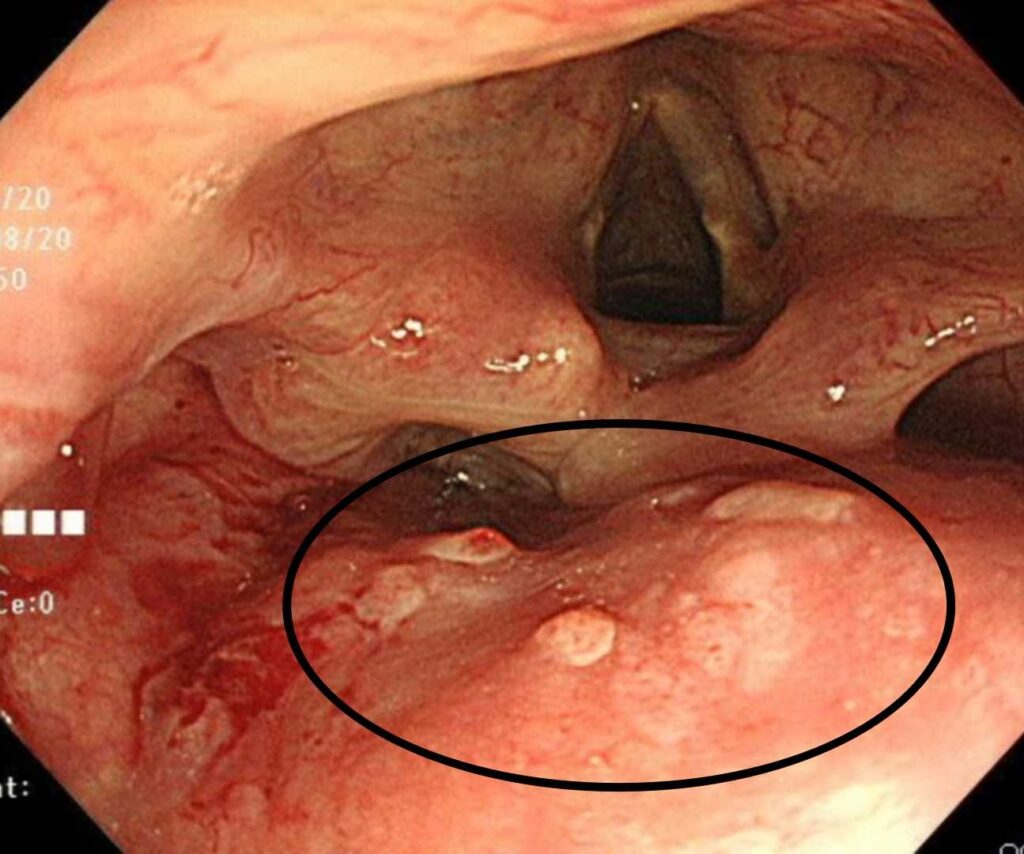

- 早期咽頭がん

定期検査で粘膜の微小な変化を拾い、内視鏡治療で完治が見込めた症例。